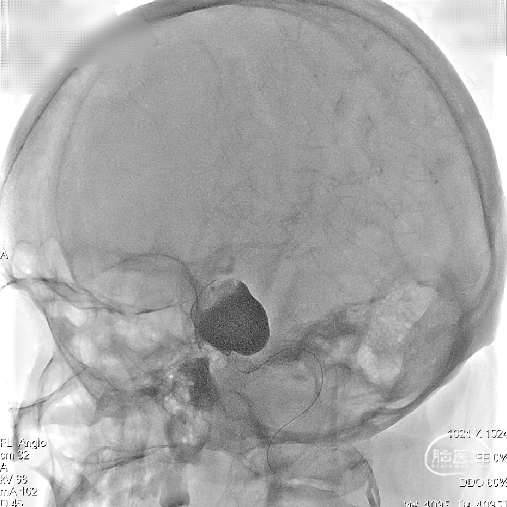

路图显示患者颈内动脉血管迂曲,瘤口处载瘤动脉呈现”S”反角弯;为使支架导管能顺利到达动脉瘤远端区域,采用囊内“成襻/解襻技术”,通过交换导丝带栓塞微导管到达动脉瘤远端,交换Fastrack-27支架微导管到达M1段。

输送支架到达支架微导管远端,缓慢回撤Fastrack-27支架微导管使支架头端打开呈“V”型,整体回撤支架系统定位于颈内动脉分叉段下约2mm位置进行锚定。

因载瘤动脉较为迂曲,为使支架头端锚定牢固, 4.5mmx45mm Tubridge血流导向密网支架前端1/3处采用稳定支撑系统逐步缓慢给张释放支架,使支架前端充分打开并与血管壁充分贴合。